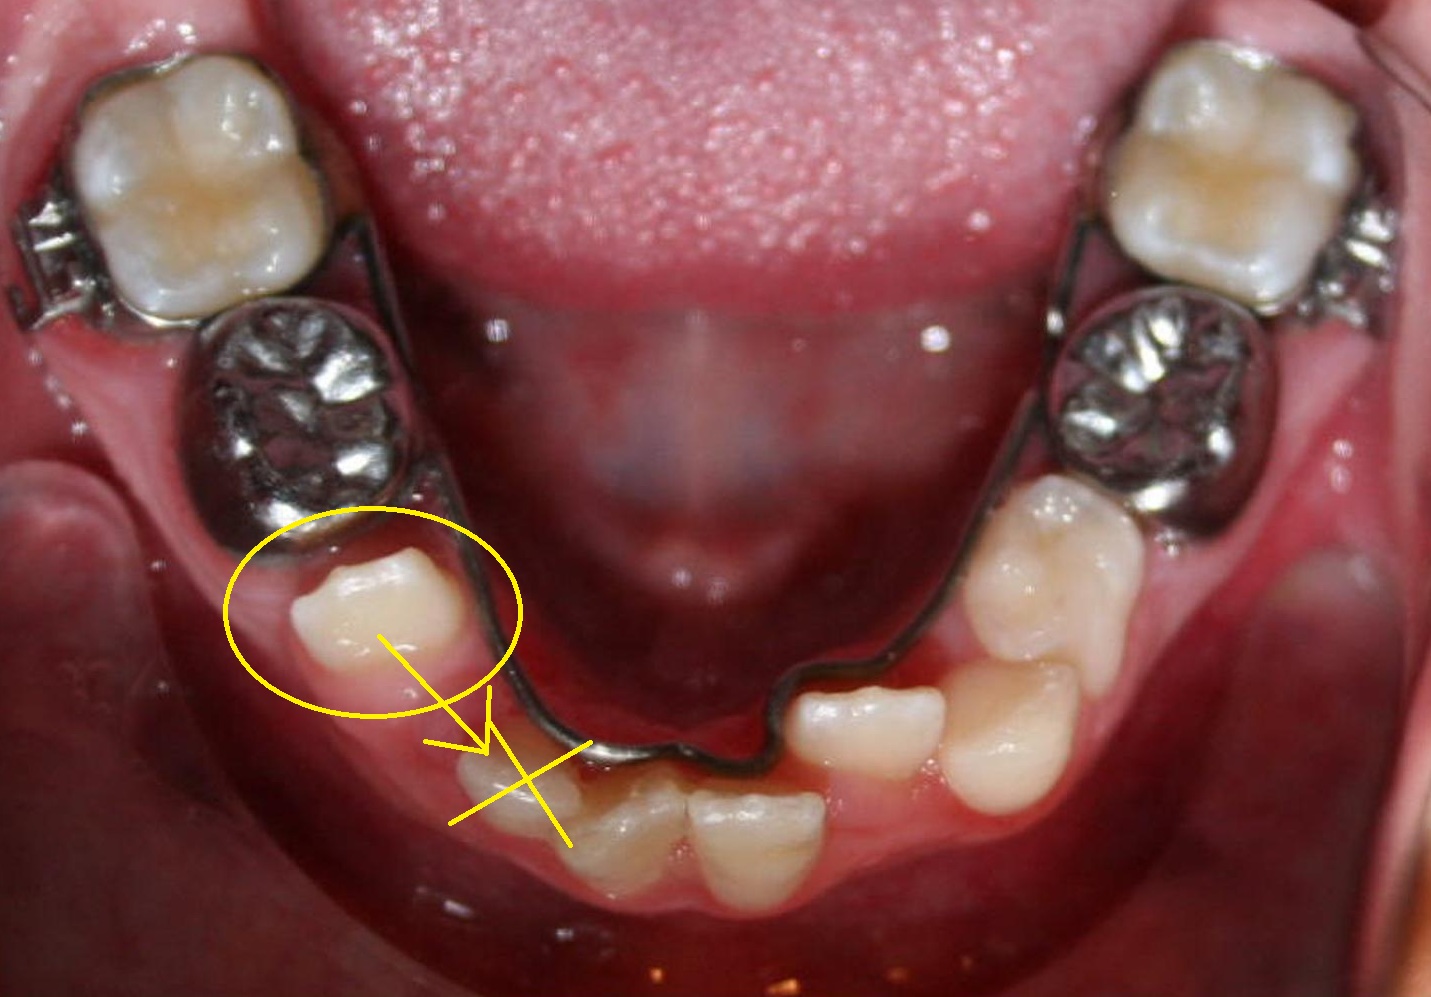

Relocation of Infrapositioned Ankylosed Teeth Description of Orthodontic Repositioning (a) the application of extremely light and. the benefits of orthodontic repositioning are linked to three key factors: during treatment, incorrect bracket placement can be corrected through bracket repositioning or wire bends. orthodontists strive for accurate bracket positioning because it makes achieving a superior occlusion easier. orthodontic repositioning principles by means of orthodontic appliance anchored to. Orthodontic Repositioning.